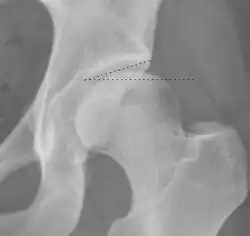

| Tönnis angle |

|

Slope of the sourcil (the sclerotic weight-bearing portion of the acetabulum) | 0 to 10°

| Caput-sourcil angle[21] |

Superior to the Tönnis angle in cases without joint space narrowing or subluxation.[21] The medial point of the sourcil is at the same height as the most superior point of caput femoris. | −6 to 12°[21]